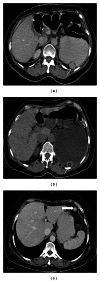

Spleen can have a wide range of anomalies including its shape, location, number, and size. Although most of these anomalies are congenital, there are also acquired types. Congenital anomalies affecting the shape of spleen are lobulations, notches, and clefts; the fusion and location anomalies of spleen are accessory spleen, splenopancreatic fusion, and wandering spleen; polysplenia can be associated with a syndrome. Splenosis and small spleen are acquired anomalies which are caused by trauma and sickle cell disease, respectively. These anomalies can be detected easily by using different imaging modalities including ultrasonography, computed tomography, magnetic resonance imaging, and also Tc-99m scintigraphy. In this pictorial essay, we review the imaging findings of these anomalies which can cause diagnostic pitfalls and be interpreted as pathologic processes.